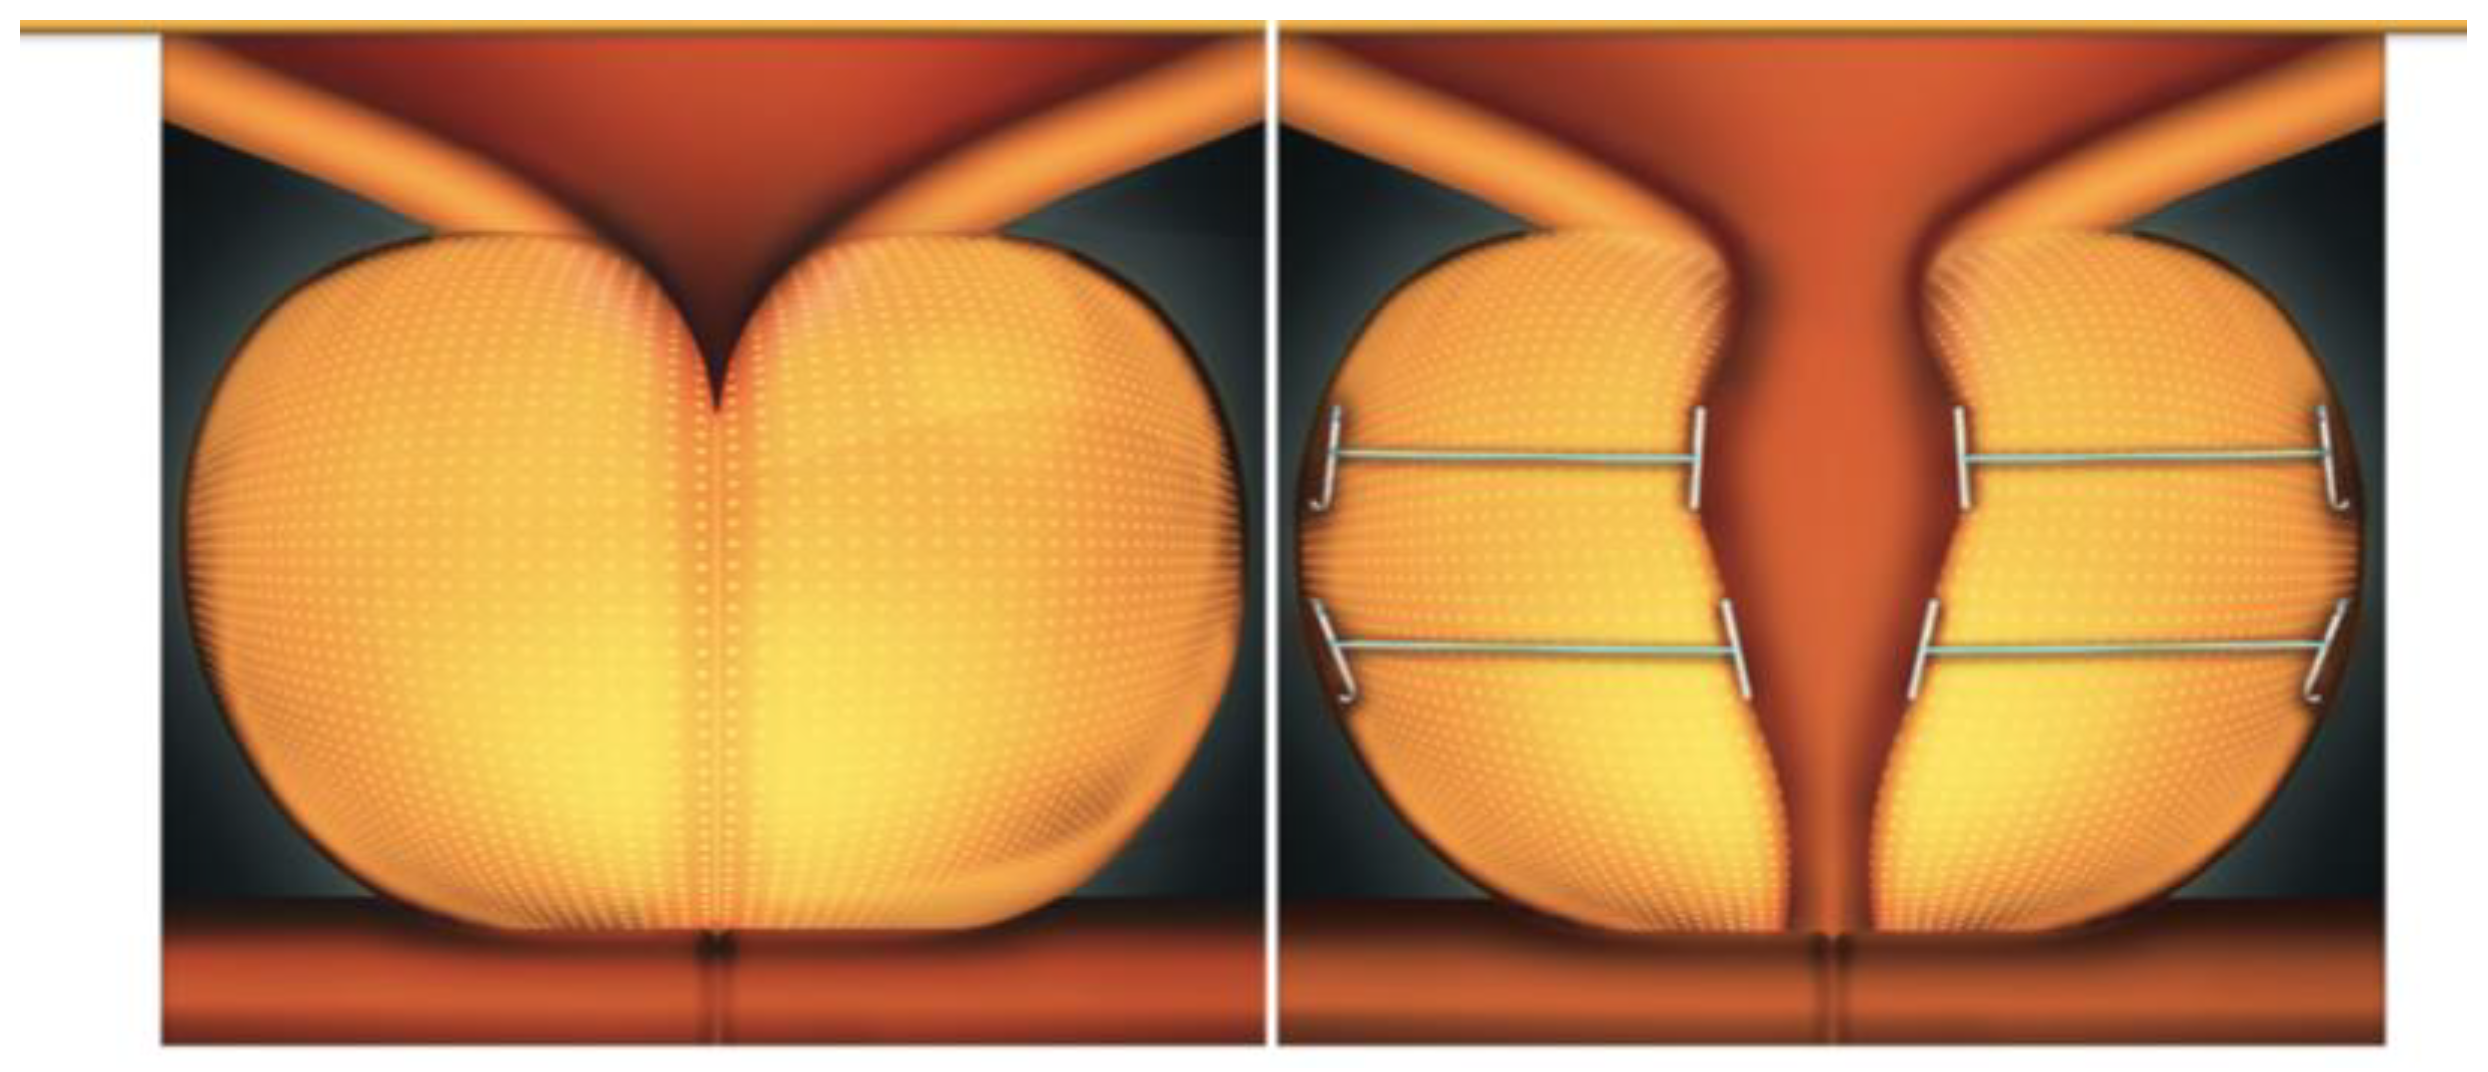

- Woo, H.H.; Huang, C.-P.; Huang, W.J.; Chang, Y.-H.; Lien, C.-S.; Chkhotua, A.; Elterman, D.S. The EXPANDER-1 trial: Introduction of the novel Urocross™ Expander System for treatment of lower urinary tract symptoms (LUTS) secondary to benign prostatic hyperplasia (BPH). Prostate Cancer Prostatic Dis. 2022, 25, 576–582. [Google Scholar] [CrossRef]

- McNicholas, T.A.; Woo, H.H.; Chin, P.T.; Bolton, D.; Arjona, M.F.; Sievert, K.-D.; Schoenthaler, M.; Wetterauer, U.; Vrijhof, E.J.; Gange, S.; et al. Minimally invasive prostatic urethral lift: Surgical technique and multinational experience. Eur. Urol. 2013, 64, 292. [Google Scholar] [CrossRef]